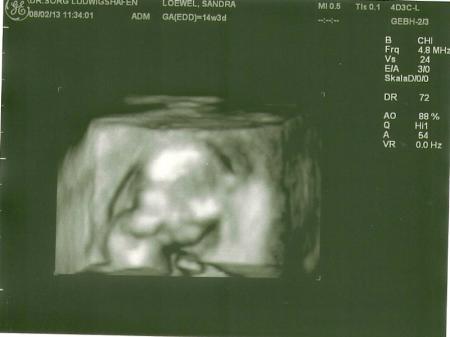

und noch eins in 3 D, da sieht es aus als ob er lächelt. LG

Bild zu